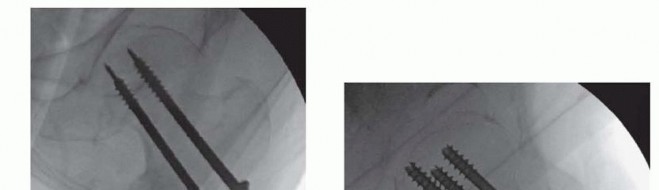

Closed Reduction and Percutaneous Fixation The patient is positioned on the fracture table and reduction is obtained as noted earlier, C-arm visualization is verified, and the leg and hip is prepared and draped in a sterile fashion. Preoperative antibiotics are given. ### Guidewire and Screw Placement Guidewires for cannulated screws are placed in line with the femoral neck axis through poke holes. The wires are placed parallel using a parallel drill guide. The standard screw arrangement is an inverted triangle of three screws. They should be positioned peripherally in the femoral neck with good cortical buttress, particularly against the inferior and posterior neck. Starting points below the lesser trochanter should be avoided owing to risk of subtrochanteric fracture postoperatively ( TECH FIG 1A-C).

TECH FIG 1 • A. Sawbones lateral view of the proximal femur showing configuration for three parallel guidewires before placement of cannulated screws. The wire starting points form an inverted triangle. B. Intraoperative AP fluoroscopic view showing position and depth of the guidewires. The inferior wire runs right along the inferior cortex of the femoral neck—the “calcar” (

arrow

). C. Intraoperative lateral fluoroscopic view showing guidewire position. The posterior wire is directly adjacent to and supported by the posterior cortex of the neck. Care is necessary to ensure that the guidewire does not go outside of the neck and then reenter the femoral head.

Once the position of the wires is verified in two planes by fluoroscopy, small (1 cm), full-depth incisions are made at each guide pin, and the soft tissues are spread to the bone. The lateral cortex may be drilled in patients with dense bone. Self-drilling, self-tapping cannulated screws are placed by power over the guidewires. Washers should be used in the more proximal, metaphyseal locations ( TECH FIG 1D,E). Screws should be long enough so that all screw threads are on the proximal (head) side of the fracture.

### TECH FIG 1 •

(continued)

D,E. Intraoperative fluoroscopic views demonstrating cannulated screw insertion over guidewires. D. AP view showing use of washers in this metaphyseal location. E. Lateral view showing parallel insertion and appropriate depth. A no. 15 blade on a long handle is positioned at the inferior margin of the base of the femoral neck on the AP fluoroscopic image. A small skin incision is made at this level, and the soft tissues are spread down to the joint capsule. With fluoroscopic verification of position, a small capsulotomy is performed to allow drainage of the hematoma from the capsule. A blunt sucker tip can be inserted through this small incision to evacuate any remaining hematoma.